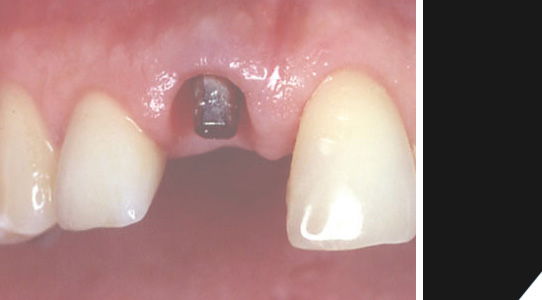

Das Implantat wurde anstelle der Wurzel in den Knochen eingebracht. Ein Zahnfleischformer bereitet die Lücke für die prothetische Versorgung vor. In dieser Phase kann man bereits von einer Übergangslösung sprechen.

Nach der Einheilphase wird ein Pfosten für die Befestigung der Krone in das Implantat eingeschraubt.

Eine Übergangslösung wird für eine kurze Zeit eingesetzt.